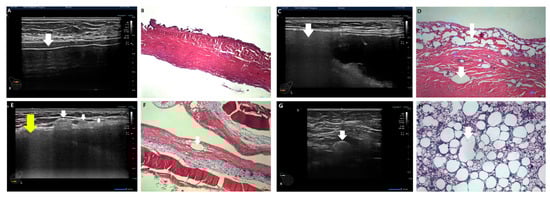

In a cross-match of all 111 capsules with ultrasonographic snowstorm sign presence, it was determined that all eighty capsules exhibited silicone embedding, inducing posterior acoustic shadowing (snowstorm signs) in ultrasonography (Figure 9). Figure 9 illustrates the study’s results, aimed at elucidating the discrepancy between the current two ultrasonographic findings and the three pathology classifications.

Therefore, pathologic intracapsular and extracapsular silicone migrations are identified as current extracapsular ruptures with positive snowstorm signs in the current definition. All fifty-eight cases of pathologic intracapsular silicone migration were matched with posterior acoustic shadowing due to silicone embedding in capsules in ultrasonography, resembling extracapsular ruptured cases.

Pathologic subcapsular rupture (SCR) corresponds to the current intracapsular rupture, with no snowstorm signs and no silicone migration to adjacent tissue or lymph nodes in ultrasonography (Figure 10A,B). Pathologic intracapsular rupture (ICR) corresponds to the current extracapsular ruptures in which there is only a snowstorm sign (+) without silicone migration to adjacent tissue or lymph nodes (Figure 10C,D). Pathologic extracapsular rupture (ECR) corresponds to the current extracapsular ruptures in which there is a snowstorm sign (+) with silicone migration to adjacent tissue or lymph nodes (Figure 10E–H). Many silicone implant ruptures are considered intracapsular, although they show snowstorm signs in ultrasonography. Since they do not show silicone migration to regional lymph nodes or adjacent tissues, this misdiagnosis caused many silicone implant ruptures to be regarded as early stages (Figure 8C).

Figure 10. Ultrasonographic images of silicone breast implant rupture. Comparison between ultrasonographic findings regarding pathology. (A) Subcapsular silicone rupture in ultrasonography (a white arrow indicates free silicone); (B) pathologic finding of subcapsular rupture (there is no silicone migration in capsule); (C) intracapsular silicone rupture in ultrasonography (a white arrow indicates free silicone); (D) pathologic finding of intracapsular silicone invasion (a white arrow indicates silicone migration); (E) extracapsular silicone migration to adjacent tissue with snowstorm sign (snowstorm sign indicated by a yellow arrow, silicone migration to adjacent tissue is indicated by a white arrow); (F) pathologic finding of extracapsular silicone migration (a white arrow characterizes silicone migration to capsules); (G) silicone migration to regional lymph nodes (a white arrow indicates snowstorm artifact); and (H) pathologic finding of silicone migration to a regional lymph node(a white arrow indicates free silicone).